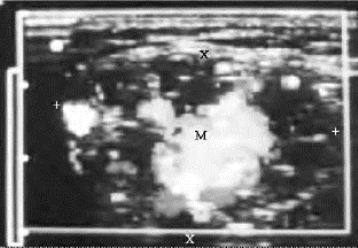

(1)海绵状血管瘤:液性暗区内显示低速静脉血流,能量图显像更为敏感。为进出瘤体的远段血管加压,可见液性暗区内瞬间静脉血流增多,明亮度增强(图6-9)。流速过低,形成血栓则无血流信号显示。

图6-9 腮腺海绵状血管瘤(加压后彩色血流明亮)(见彩图4)